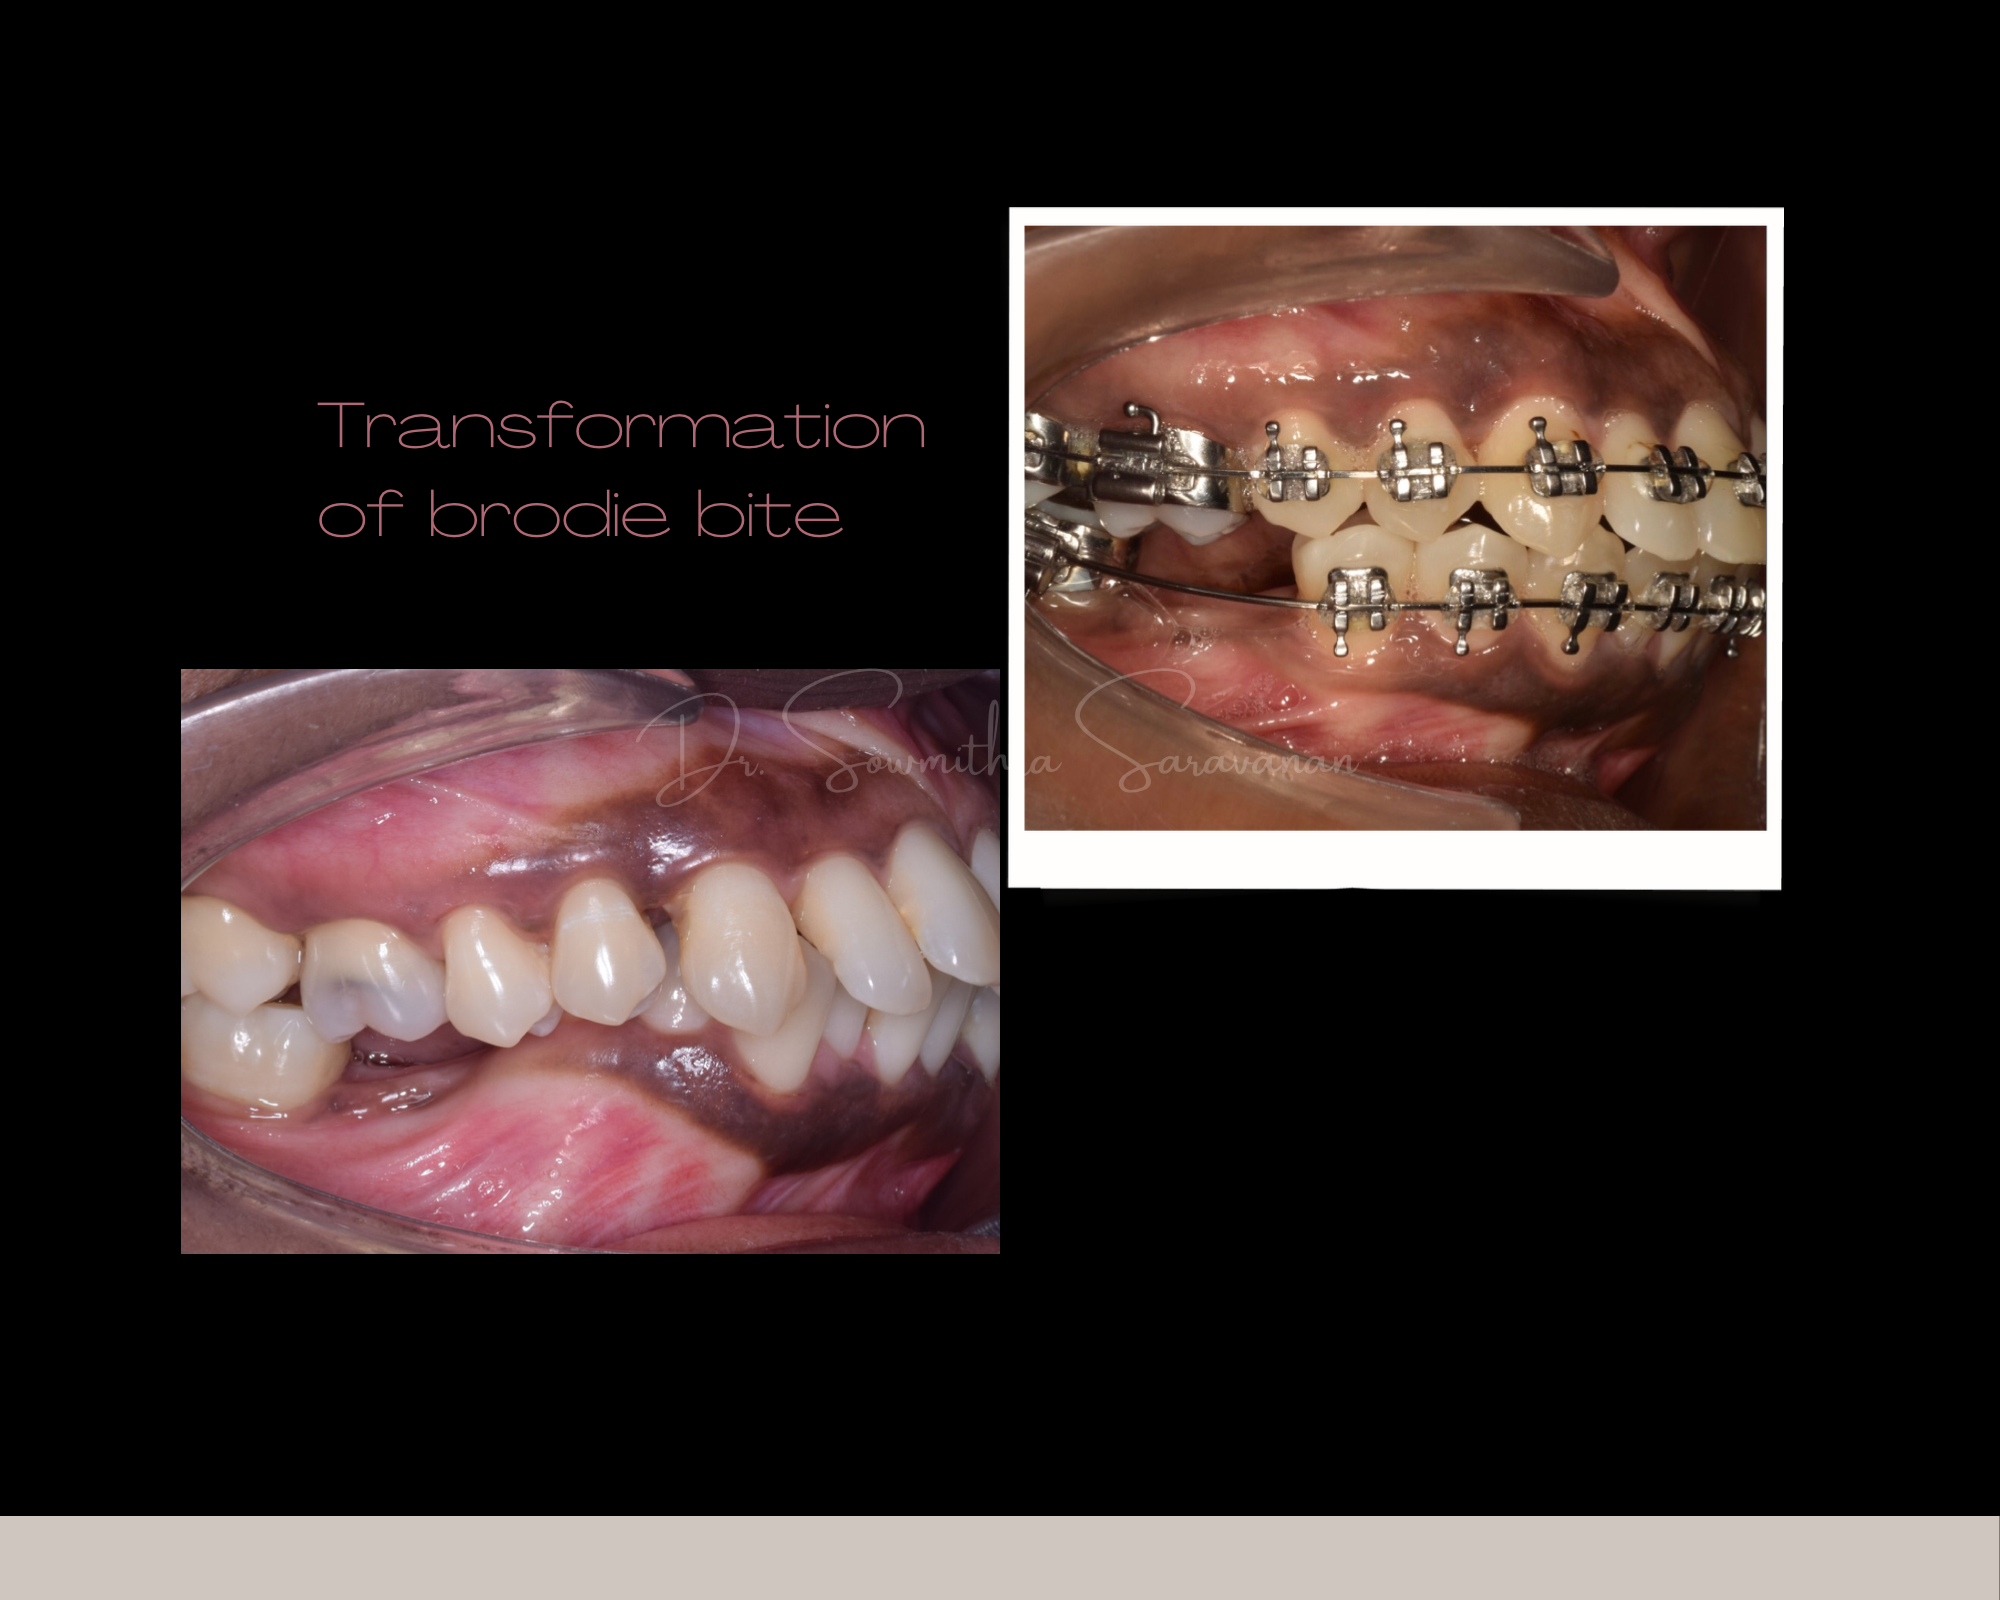

THE CROSSBITE CORRECTION

THE CROSSBITE CORRECTION